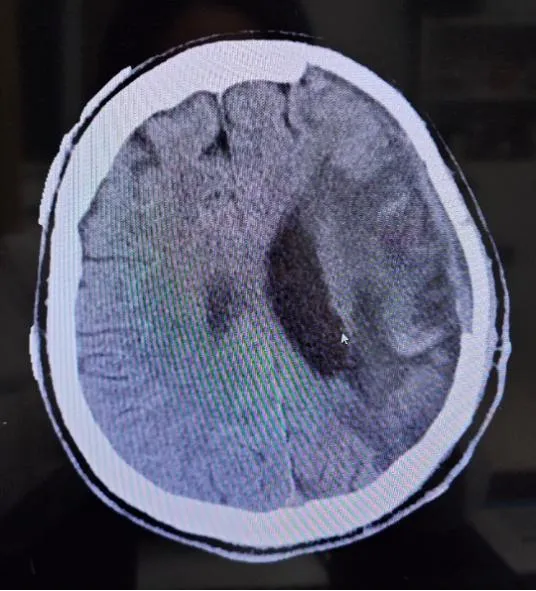

男性,27岁,2个月前因突发脑出血,当地医院行去骨瓣减压术+颅内血肿清除术+硬脑膜修补术,现为颅骨修补术前来我院,考虑年轻男性患者,术后需继续经颅磁刺激治疗,以改善认知功能,恢复患侧肢体功能障碍,刘博主任团队全面评估,决定采用全PEEK系列整体解决方案。手术过程顺利,术后患者头颅恢复原貌,头颅CT示PEEK骨板在位,未见出血和皮下积液。

术前CT